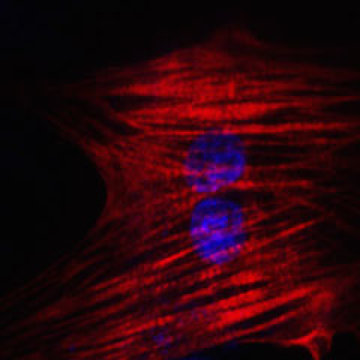

En el estudio de Science, dirigido por el primer autor Nan Cao, postdoc en el laboratorio de Ding, los investigadores utilizaron un cóctel de nueve productos químicos para transformar las células de piel humana en células del corazón. Por ensayo y error, encontraron la mejor combinación de productos químicos para comenzar el proceso, cambiando las células a un estado parecido al de las células madre multipotentes, que pueden convertirse en muchos tipos diferentes de células en un órgano en particular.

Un segundo cóctel de sustancias químicas y factores de crecimiento ayudó a las células a convertirse en células musculares del corazón.

Con este método, más de 97% de las células comenzaron a latir, una característica de las células del corazón completamente desarrolladas y sanas. Las células también respondieron apropiadamente a las hormonas, y molecularmente, se parecían a las células del músculo del corazón, no a las células de la piel. Es más, cuando las células fueron trasplantadas a un corazón de ratón al inicio del proceso, evolucionaron a células musculares del corazón de aspecto saludable.

En el estudio de Science, dirigido por el primer autor Nan Cao, postdoc en el laboratorio de Ding, los investigadores utilizaron un cóctel de nueve productos químicos para transformar las células de piel humana en células del corazón. Por ensayo y error, encontraron la mejor combinación de productos químicos para comenzar el proceso, cambiando las células a un estado parecido al de las células madre multipotentes, que pueden convertirse en muchos tipos diferentes de células en un órgano en particular.

Un segundo cóctel de sustancias químicas y factores de crecimiento ayudó a las células a convertirse en células musculares del corazón.

Con este método, más de 97% de las células comenzaron a latir, una característica de las células del corazón completamente desarrolladas y sanas. Las células también respondieron apropiadamente a las hormonas, y molecularmente, se parecían a las células del músculo del corazón, no a las células de la piel. Es más, cuando las células fueron trasplantadas a un corazón de ratón al inicio del proceso, evolucionaron a células musculares del corazón de aspecto saludable.